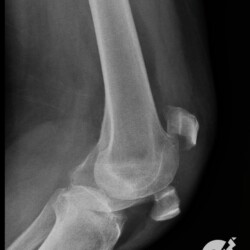

Fratura da patela com importante desvio e fratura cominutiva do 1/3 proximal da tíbia comprometendo a eminência intercondiliana.